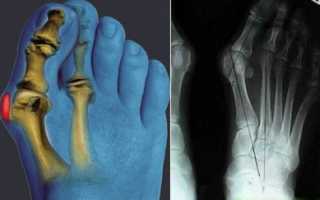

- Артродез (чаще всего выполняется при поражении мелких суставов пальцев рук или ног, а также при проблемах с голеностопом);